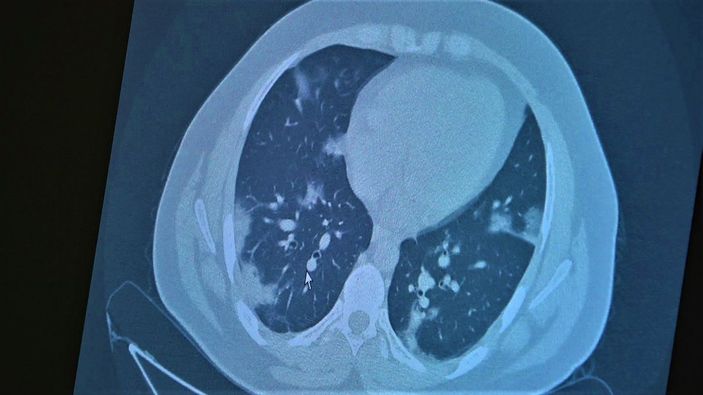

Mutasyon geçiren koronavirüsün, artık aşısız çocuklarda da ciddi zararlara yol açtığını belirten Prof. Dr. Özkaya, 11 ve 14 yaşlarında korona geçirmiş çocukların akciğer tomografisini gösterdi.

Çocukların akciğer tomografilerini inceleyen Özkaya, açıklamalarına şu ifadeler ile devam etti:

“11 yaşında kovid pozitif bir öğrencimiz, yüksek ateş ve nefes darlığı ile bize geldi. Ciddi akciğer tutulumu var. Geçen yıl ‘bu çocuklar hastalıktan etkilenmiyor’ diyorduk. Bu çocukta görüyorsunuz buzlu camlar ve konsolidasyon alanlarla seyrediyor. Geçen yıl bu şekilde çok çocuk görmüyorduk. Önümüzdeki aylarda bu şekilde devam ederse çocuklarımızı kaybetmeye bile başlayabiliriz.

14 yaşında pozitif olan bir diğer çocuğumuz ise aşı randevusu almış ama aşısını olmadan ateş ve öksürükle başvurdu. Halen şanslıyız. Çocuklar çok hızlı tedaviye yanıt veriyor. Düzeldi. Çekilen tomografisinde ise bilaterel yaygın tutulumları vardı. Bu ise 24 yaşında genç hastanın akciğer tomografisi. Bu kişide yaygın akciğer tutulumları görüldü. Bunu da tedavi ettik. Önümüzdeki aylarda ne getirecek ne götürecek beraber göreceğiz. Özellikle havaların soğumasıyla kapalı ortamlarda geçilen zamanın ve kalabalıkların etkisiyle vaka sayılarının önümüzdeki günlerde artacağını biliyoruz. Şu an gerçekten hastalık gençlerde 30 -40 yaş altı gençlerde görülmeye başladı. Poliklinik şartlarında olanların büyük bir kısmı 30 yaş altı hastalar. Servislerde yatanlarda orta yaş ve altı nüfus. Yoğun bakımda yatanların büyük bir kısmı ise aşısız erişkin insanlardan oluşuyor.”